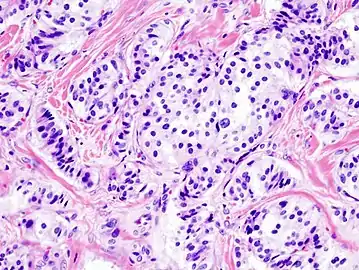

| Pathology of pancreatic endocrine tumour (insulinoma). | |